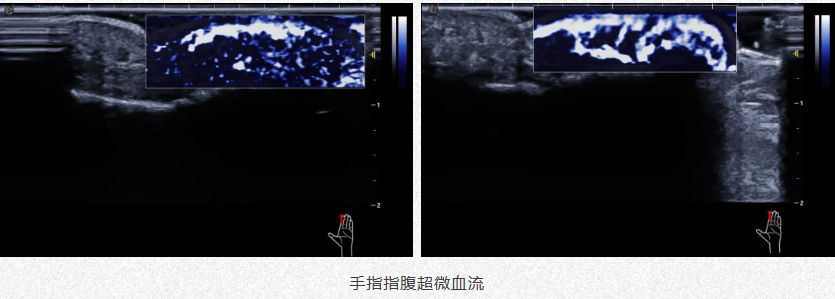

肌骨系统炎症监测

1.前期显示患处血供情况助力医生诊断。

2.中期精准定位避开血管防药物中毒。

3.后期评估疗效随访监测。